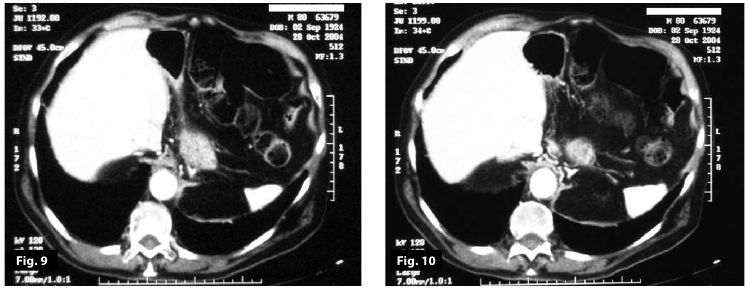

Figure9

Figure10

Figure9-10